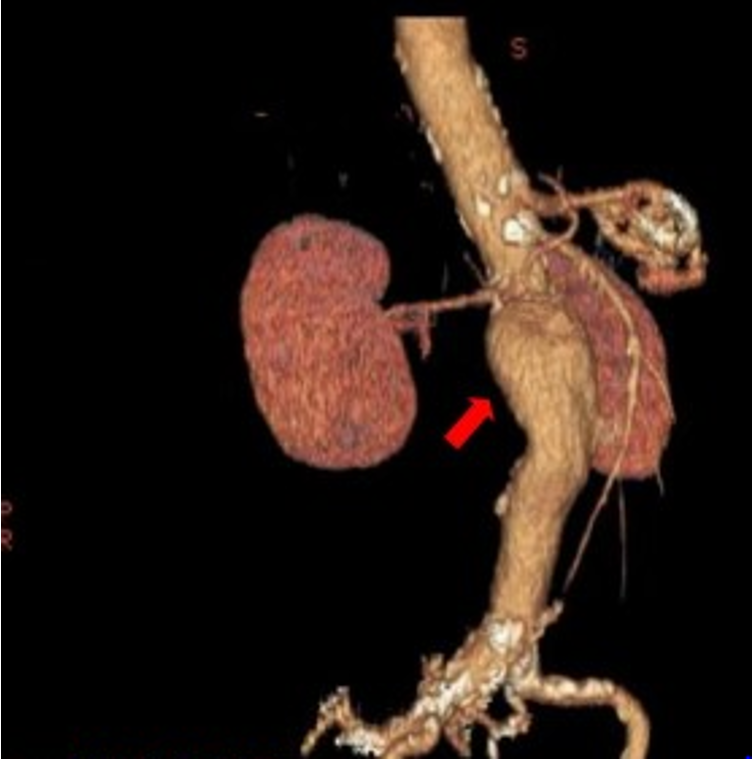

What does this CT refer to

Abdominal Aortic Aneurysm

What does this CT angiography refer to

Aortic aneurysm